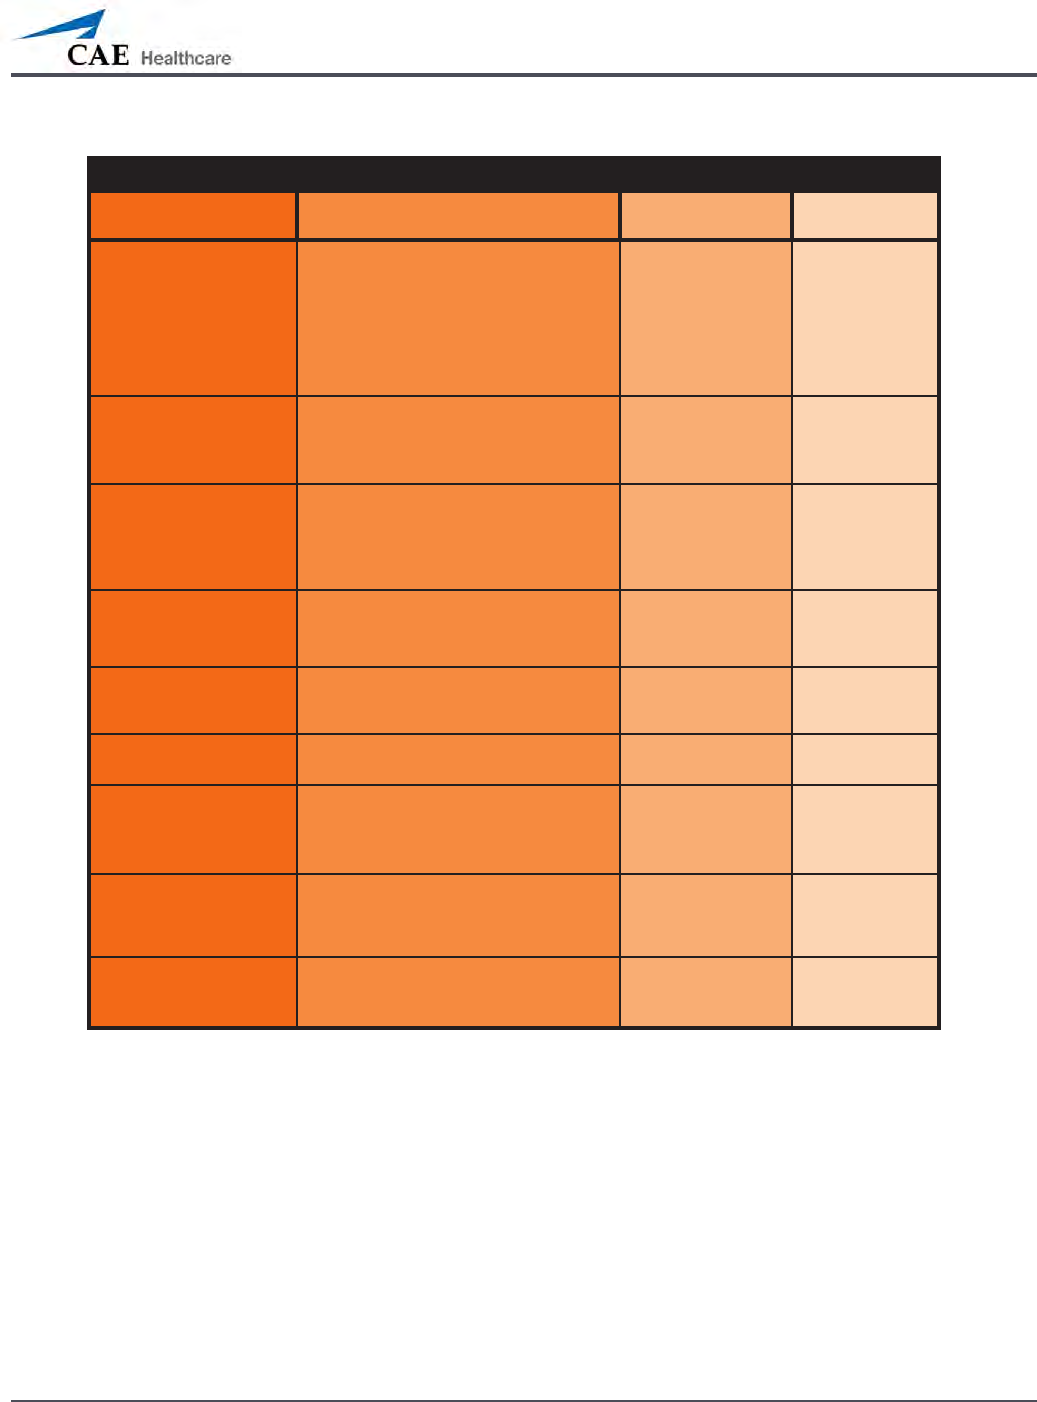

Airway Features

Anatomy, Physiology

and Clinical Signs Clinical Interventions, Patient

Monitoring and Scenarios. Software Control Manual

Control

Realistic Upper

Airway (Oropharynx,

Nasopharynx and Larynx)

(Prehospital only)

Allows direct laryngoscopy, oral and

nasal intubation and use of specialty

airway devices. Simulator detects

and responds appropriately to right

mainstem intubation. Endobronchial

intubation results in unilateral chest

excursion and breath sounds.

None required. None required.

Trachea, Left and Right

Mainstem Bronchi

(Prehospital only)

Tracheal intubation results in bilateral

chest excursion and breath sounds. None required. None required.

Airway Management and

Ventilation

Alveolar and arterial gas concentrations

appropriately reect the ecacy of

ventilation and oxygen administration.

Oxygen

administration input

by the instructor.

VIEW: Respiratory

None required.

Gastric Distention

(Prehospital only)

Esophageal intubation results in gastric

distension and the absence of breath

sounds, chest excursion and CO2 output.

None required. None required.

Breakaway Teeth

(Prehospital only)

Upper front teeth can be dislodged if

laryngoscopy is performed incorrectly. None required. See Breakaway

Teeth

Tongue Edema

(On/O)

Hinders, but does not prevent,

intubation. VIEW: Respiratory None required.

Posterior Pharynx

Swelling

(Prehospital only)

Obstructs view of larynx to prevent

intubation, but allows mask ventilation

“can’t intubate, can ventilate” scenario.

VIEW: Respiratory None required.

Laryngospasm

(Prehospital only)

Closes vocal cords and prevents

intubation and ventilation. When used

with posterior pharynx swelling, creates

a “can’t intubate, can’t ventilate” scenario.

VIEW: Respiratory None required.

Cricothyroid Membrane Allows needle cricothyrotomy,

transtracheal jet ventilation, retrograde

wire techniques and cricothyrotomy.

None required. See

Cricothyrotomy,

132